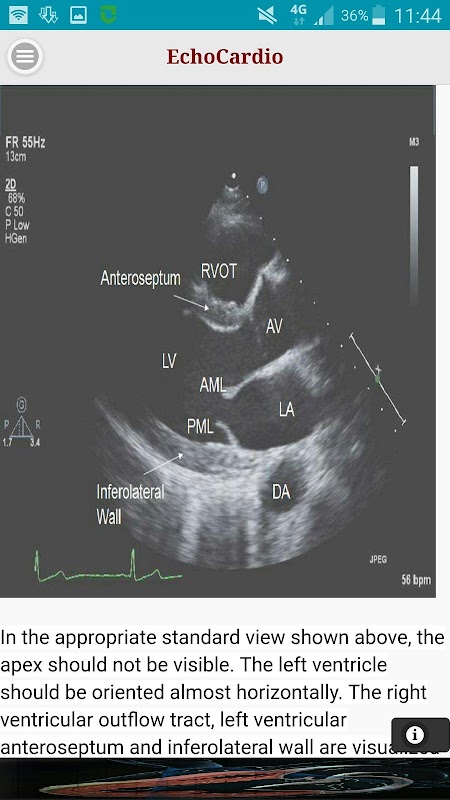

Transthoracic echocardiography (TTE) adalah pemeriksaan USG jantung paling umum dilakukan. Sebuah transthoracic echocardiogram kualitas tinggi dapat dilakukan dengan cepat di samping tempat tidur dan memiliki potensi untuk secara komprehensif mengevaluasi kiri dan kanan sistolik ventrikel dan fungsi diastolik, gerakan dinding regional, penyakit jantung katup, dan penyakit perikardium.

Parasternal panjang Axis